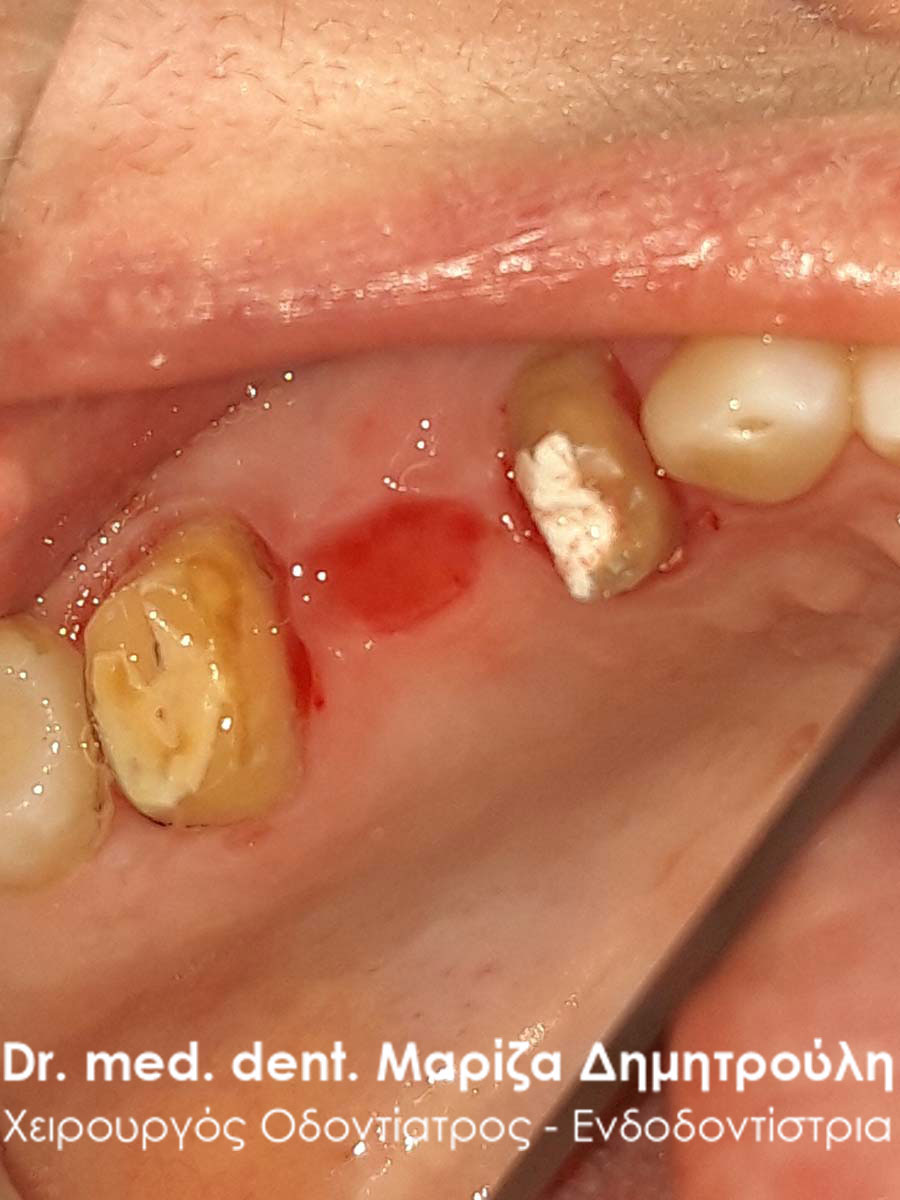

Η ασθενής προσήλθε στο ιατρείο με απόστημα / πρήξιμο στην αριστερή πλευρά της κάτω γνάθου. Μετά την κλινική εξέταση της περιοχής διαπιστώθηκε έντονη κινητικότητα στον κάτω αριστερό δεύτερο προγόμφιο, ο οποίος έφερε μεταλλοκεραμική θήκη. Μετά από συνεννόηση με την ασθενή αποφασίστηκε η αφαίρεση της παλιάς θήκης, ώστε να διαπιστωθεί τι συμβαίνει με το υποκείμενο δόντι στήριγμα και αν ήταν δυνατόν να κρατηθεί το δόντι στο στόμα.

Αρχικά χορηγήθηκε τοπική αναισθησία στην ασθενή, αφαιρέθηκε η στεφάνη δοντιού και διαπιστώθηκε οτι το δόντι στήριγμα είχε σπάσει στο ύψος των ούλων. Σύμφωνα με τα νέα κλινικά δεδομένα το δόντι μπορούσε να σωθεί για αυτό και πραγματοποιήθηκε η ανασύσταση του δοντιού με ενδοριζικό άξονα υαλονημάτων. Ακολούθως το δόντι τροχίστηκε και στη συνέχεια λήφθηκαν αποτυπώματα για τη κατασκευή νέας θήκης δοντιού από τον οδοντοτεχνίτη. Όταν η θήκη ήταν έτοιμη ατή συγκολλήθηκε μόνιμα στο δόντι.

Αξίζει να σημειωθεί οτι αμέσως μετά την αφαίρεση της παλιάς θήκης και τη νέα ανασύσταση του δοντιού υποχώρησε άμεσα η φλεγμονή των ούλων στην περιοχή του δεύτερου προγόμφιου. Η ασθενής είναι ευχαριστημένη τόσο με το λειτουργικό όσο και με το αισθητικό αποτέλεσμα της νέας θήκης δοντιού.

Αρχική εικόνα του αποστήματος δοντιού